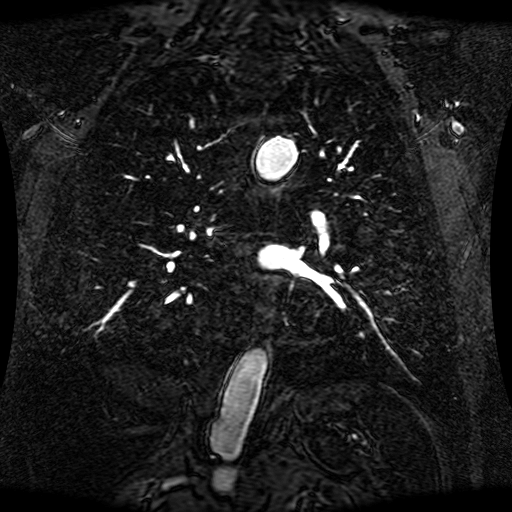

Data Description

These magnetic resonance angiography (MRA) images show coronal slices acquired from consecutive anteroposterior positions within the torso. The study was performed on a 1.5T General Electric (GE) Signa imaging system with gadolinium-contrast-enhancement for visualization of the cardiopulmonary vasculature. The pulse sequence used was a 3D time-of-flight fast spoiled gradient recalled acquisition in steady state (FSPGR, TR=6.3, TE=1.4, NEX=1, FOV = 40cm, slice thickness = 1.2mm).

This sample image contains 76 frames. It is available in DICOM format (E1154S7I.dcm), as an animated GIF (E1154S7I.gif), as .ogg, .mp4, .webm, and .swf animations (one of which is shown above), or as individual PNG-format frames (see below).